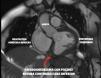

Mujer de 62 años, sin antecedentes personales, consulta por epigastralgia de cuatro días, sufriendo un ictus lacunar hemi-motor puro derecho con tomografía computarizada multimodal anodino. En el electrocardiograma se observa elevación del ST inferior con ondas Q, ingresando en la unidad de cuidados intensivos. En la ecocardiografía transtorácica se objetiva comunicación interventricular septo-basal con cara inferior aquinética, adelgazada e hiperecogénica sugestiva de pseudoaneurisma con posible ruptura miocárdica contenida (fig. 1, Video 1). Se desestima cirugía emergente ante clínica neurológica y riesgo quirúrgico por friabilidad de tejidos. A la espera de decisión final, se realiza resonancia magnética nuclear cardiaca (fig. 2), tras la que sufre parada cardiorrespiratoria en actividad eléctrica sin pulso por taponamiento con reanimación infructuosa (fig. 3, Videos 2,3). Las complicaciones mecánicas postinfarto agudo de miocardio, aunque inusuales hoy en día, siguen siendo una patología potencialmente mortal y tiempo-dependientes, donde las técnicas de imagen como la ecocardiografía siguen jugando un papel fundamental.